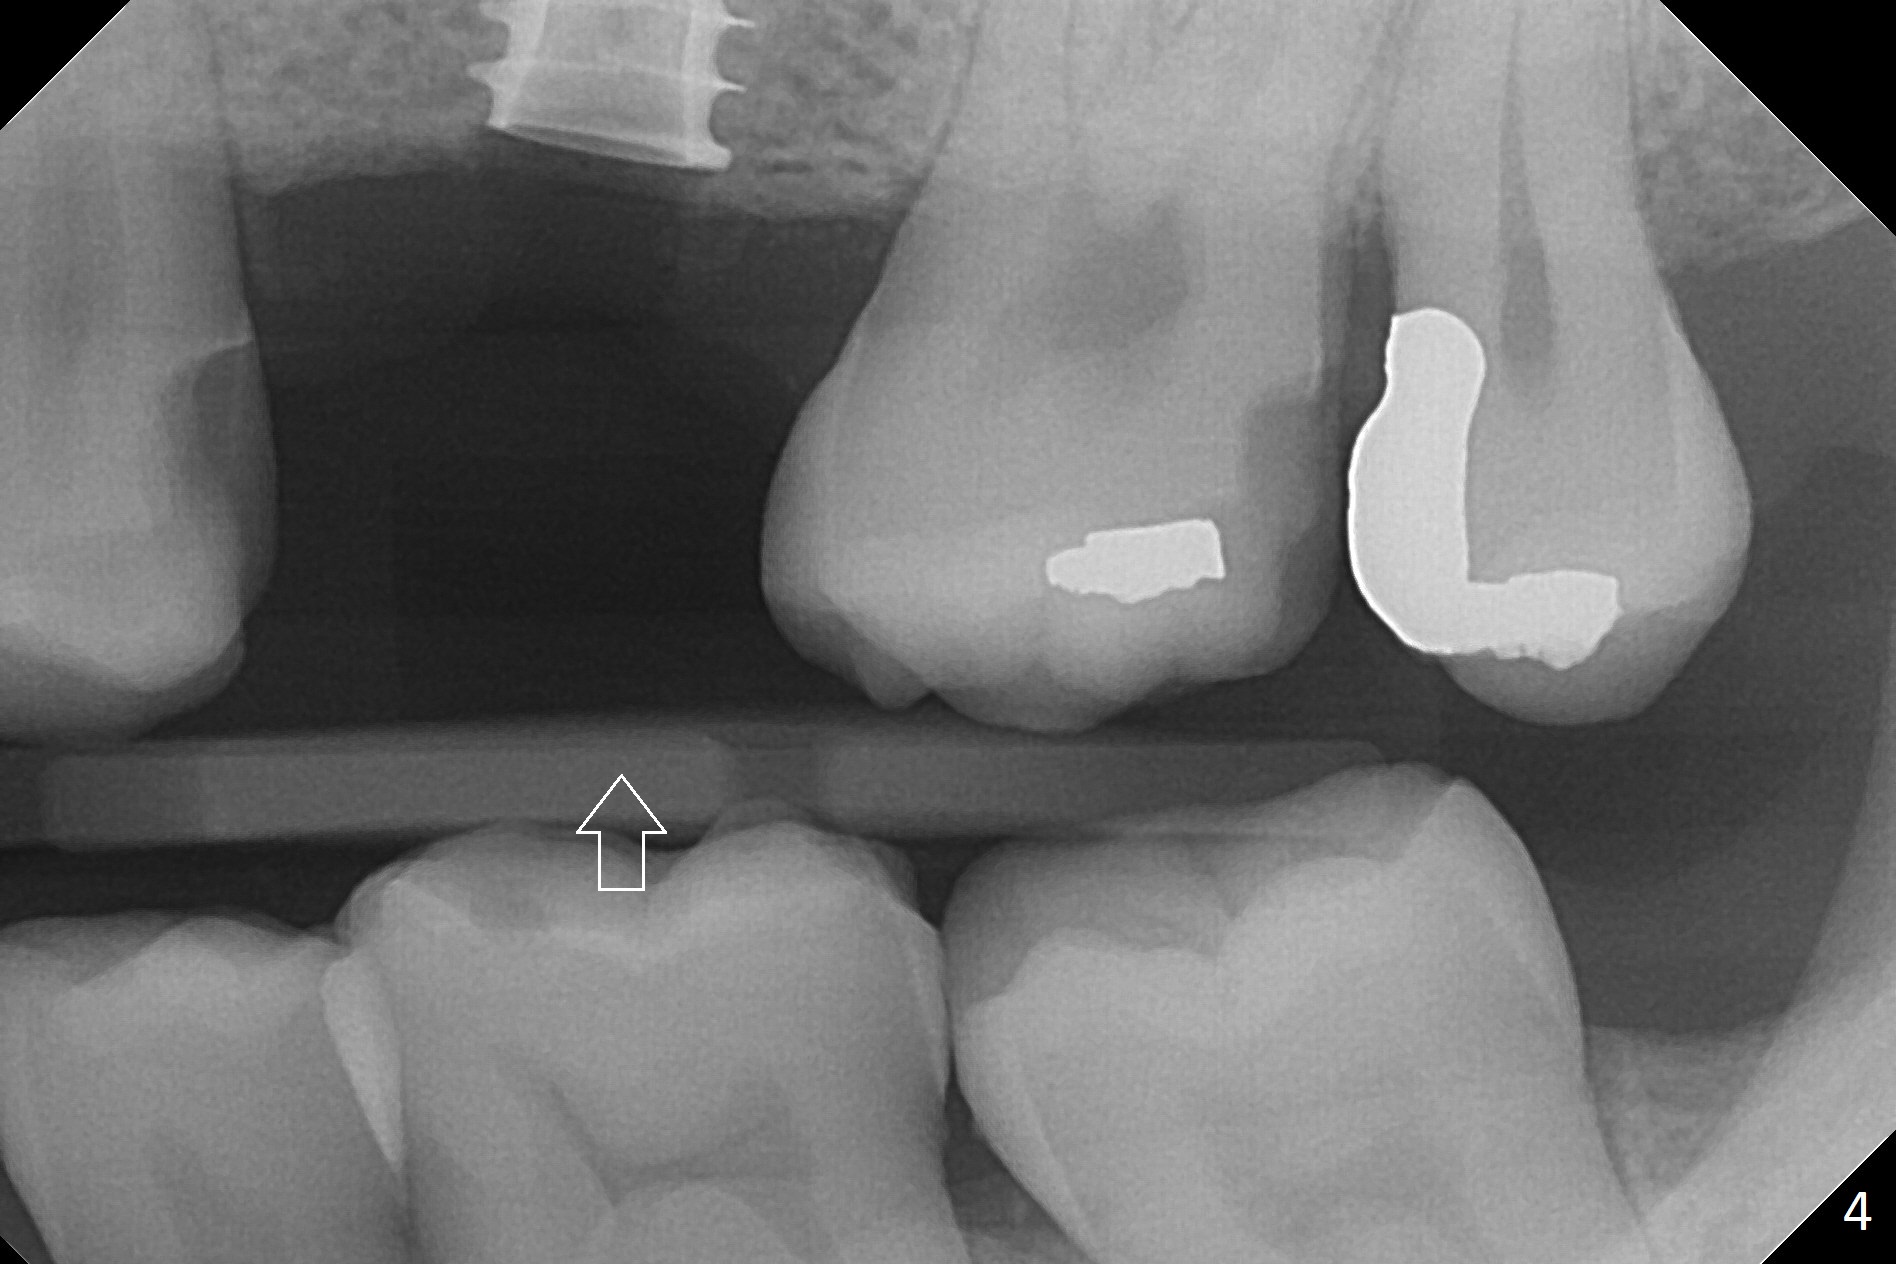

While the base of the ridge at #14 is wide, the top is moderate. IBS Magic Split is applied to gain access and test bone density (flapless). In fact the bone is hard. A 1.6 mm pilot drill is used for 9 mm (gingival level), followed by insertion of a parallel pin (Fig.1). Following Magic Expander 3.0 mm and Magic Drill 3.8 mm for ~ 11 mm (with empty feeling without air leak), a 4x11 mm dummy implant is placed with 25 Ncm (Fig.2). After insertion of a 4.5x11 mm dummy implant at 9 mm (35 Ncm; for further bone expansion), one piece of PRF plug and 1 piece of PRF membrane are pushed into the osteotomy, followed by allograft mixed with autogenous bone for sinus lift and placement of a 5x9 mm implant (Fig.3,4 with insertion torque >50 Ncm). A 6x4(2) mm abutment is placed for fabrication of an immediate provisional (Fig.5 P). There is no nasal hemorrhage postop. PRF membrane and plug are used to prevent and repair sinus membrane perforation and facilitate wound healing. There is mild bone resorption at the crest 11 months postop (Fig.6,7). The bone resorption seems to be worse 8 months post cementation (Fig.8,9); in fact the abutment screw is loose.